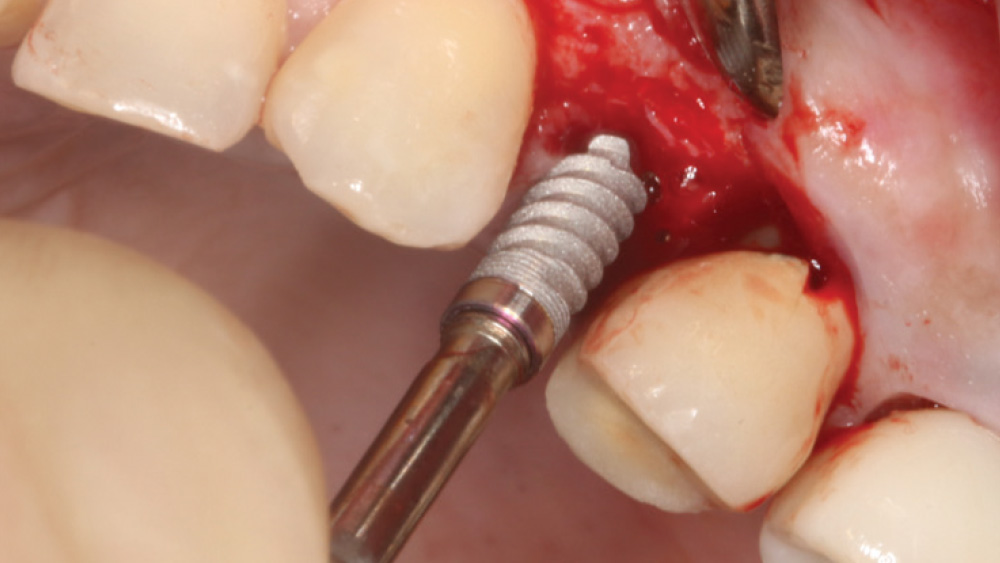

When the attached tissue is minimal, a flap procedure allows the surgeon to reposition the flap to create more attached gingiva and improve the interdental papillae at the implant site. Reflecting a gingival flap also enables the practitioner to more clearly see the final position of the implant at the crest of the bone. If it’s necessary to visualize the bone during the surgical procedure due to uncertain ridge width or height, flap reflection is the safest, most predictable approach.

The following case, which I performed alongside Dr. Stephanie Tilley of Pensacola, Florida, illustrates the use of both surgical techniques for the same patient, who presented with edentulous spaces in the areas of both right and left maxillary first bicuspids. Due to varying soft-tissue volume on each side of the arch, implant surgery was performed using a flapless procedure for one site, while the attached gingiva was reflected to expose the available hard tissue for the other. As a result of proper site evaluation, treatment planning and restorative-driven implant placement, both surgical techniques led to successful outcomes for the patient.